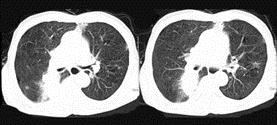

问题 72岁,男,呼吸急促、气喘4个月,请结合胸片和CT,选出最可能的诊断 ( )

选项 A、韦格肉芽肿 B、支气管腺瘤 C、错构瘤 D、肺结核 E、肺癌

答案 E